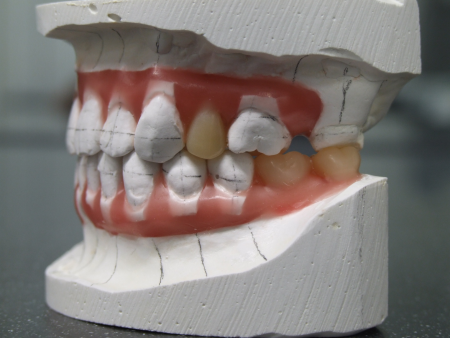

挺出した左上奥歯(第1大臼歯)がこの患者さまにとって最も大きな問題でした。PAというセファロ分析では、この伸び出た左上奥歯によって左右の上顎第一大臼歯結んだ咬合平面が極端に右上がりになっていました (キャント)。このままインプラントの歯をいれてしまうと顎関節症だけでなく、顔が歪んでしまうリスクもあります。しかし、全体的には咬合高径が低下した状態であったため、適切な咬合高径と咬合平面を矯正治療にてバランスよく設定するのは難しいケースでした。咬合治療の進め方としてはまず、最初に適切な咬合高径、咬合平面を決定することが重要になります。これは総入れ歯の治療と同様です(要素A)。

次にアンテリアガイダンスの設定を行なっていきます。適切な咬合高径の設定・咬合挙上により下顎がスイングバックしているため、上顎の前歯は後方に移動しています。上下の歯の中心を揃えるのに苦労しました(要素B)。

PA分析では、挺出した左上第1大臼歯によって左右の上顎第一大臼を歯結んだ咬合平面に極端な右上がりの傾斜(キャント)が発生しています。咬合治療の進め方としてはまず左上ブリッジの支台歯(犬歯、第2小臼歯)をTEKに変更(一般歯科担当医)とインプラント4本それぞれにTEKの装着(インプラント専門医)を行いました。上下に矯正装置を装着するタイミングでオーバーレイテクニックを行い、下顎骨のスイングバック量を評価しながら咬合治療のゴール設定である咬合平面、咬合高径を決定します。この咬合平面を基準に左上第1大臼歯の圧下を行っています。